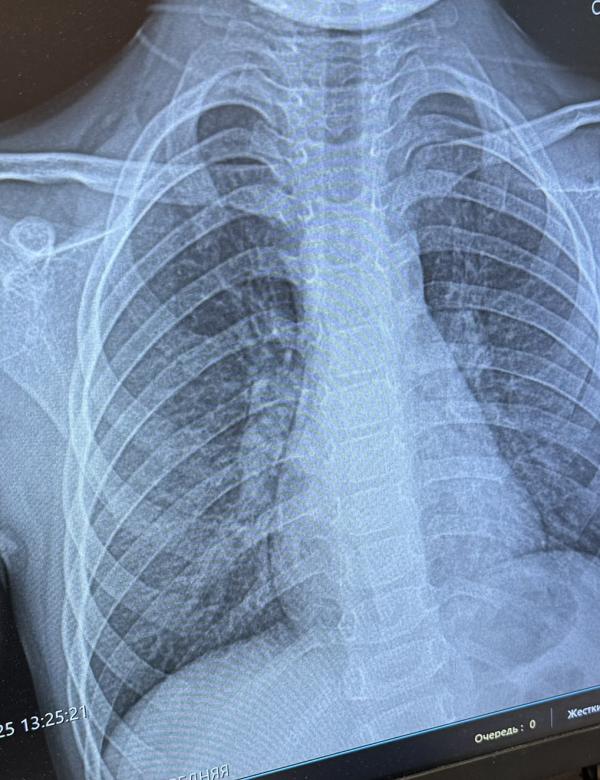

Симптомы пневмонии у детей: как распознать и что делать

Девочки кто понимает,есть пневмония ?